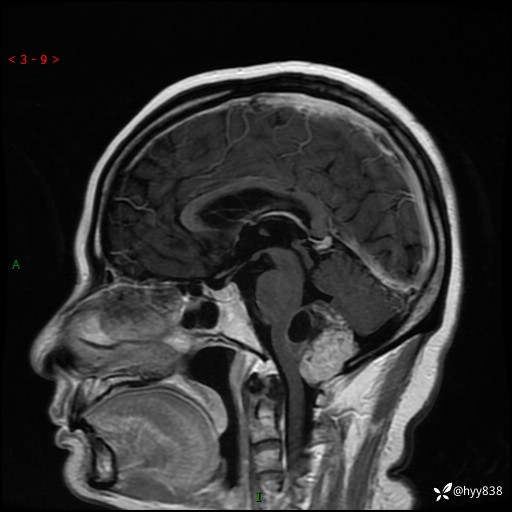

性别:女

年龄:47岁

简要病史:头晕1年余,间断恶心不伴呕吐

颅脑MRI平扫+DWI

轴内、轴外占位

轴内或轴外肿瘤